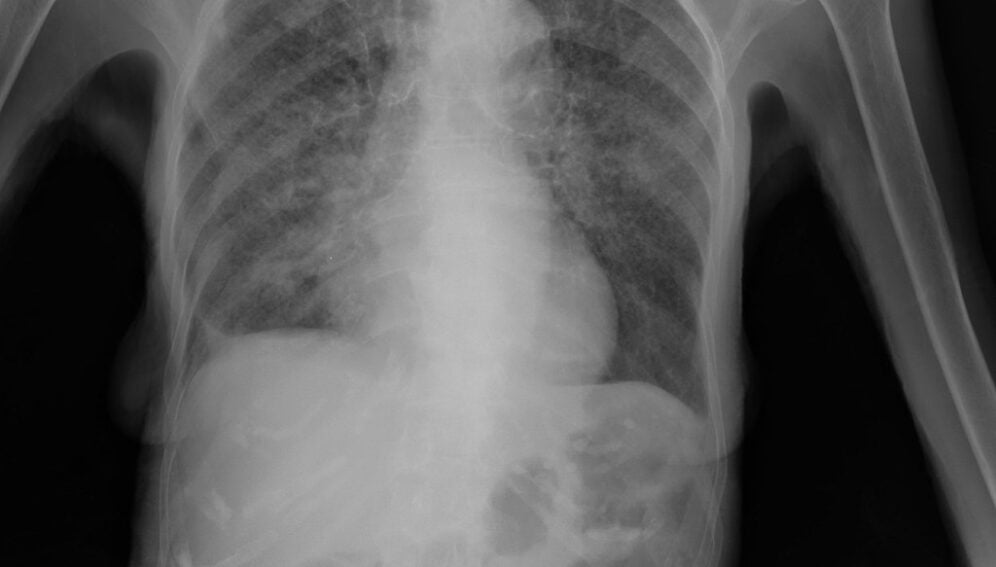

La tuberculose commence souvent par des signes discrets : une toux qui s’éternise, une fièvre légère, des sueurs nocturnes, et une perte de poids progressive. Sans test, ces symptômes se confondent avec d’autres maladies.

Le paradoxe de la tuberculose aujourd’hui n’est pas l’absence d’outils : nous disposons de tests moléculaires rapides, de radiographies numériques mobiles, de traitements efficaces et d’un succès thérapeutique national de 90 %.

Pendant des décennies, le diagnostic reposait sur une recherche laborieuse des bactéries de la tuberculose au microscope, un processus à la fois lent et incertain. Celui-ci est désormais progressivement remplacé par des diagnostics moléculaires recommandés par l’Organisation mondiale de la santé, capables de confirmer un cas en quelques heures — voire en quelques minutes.